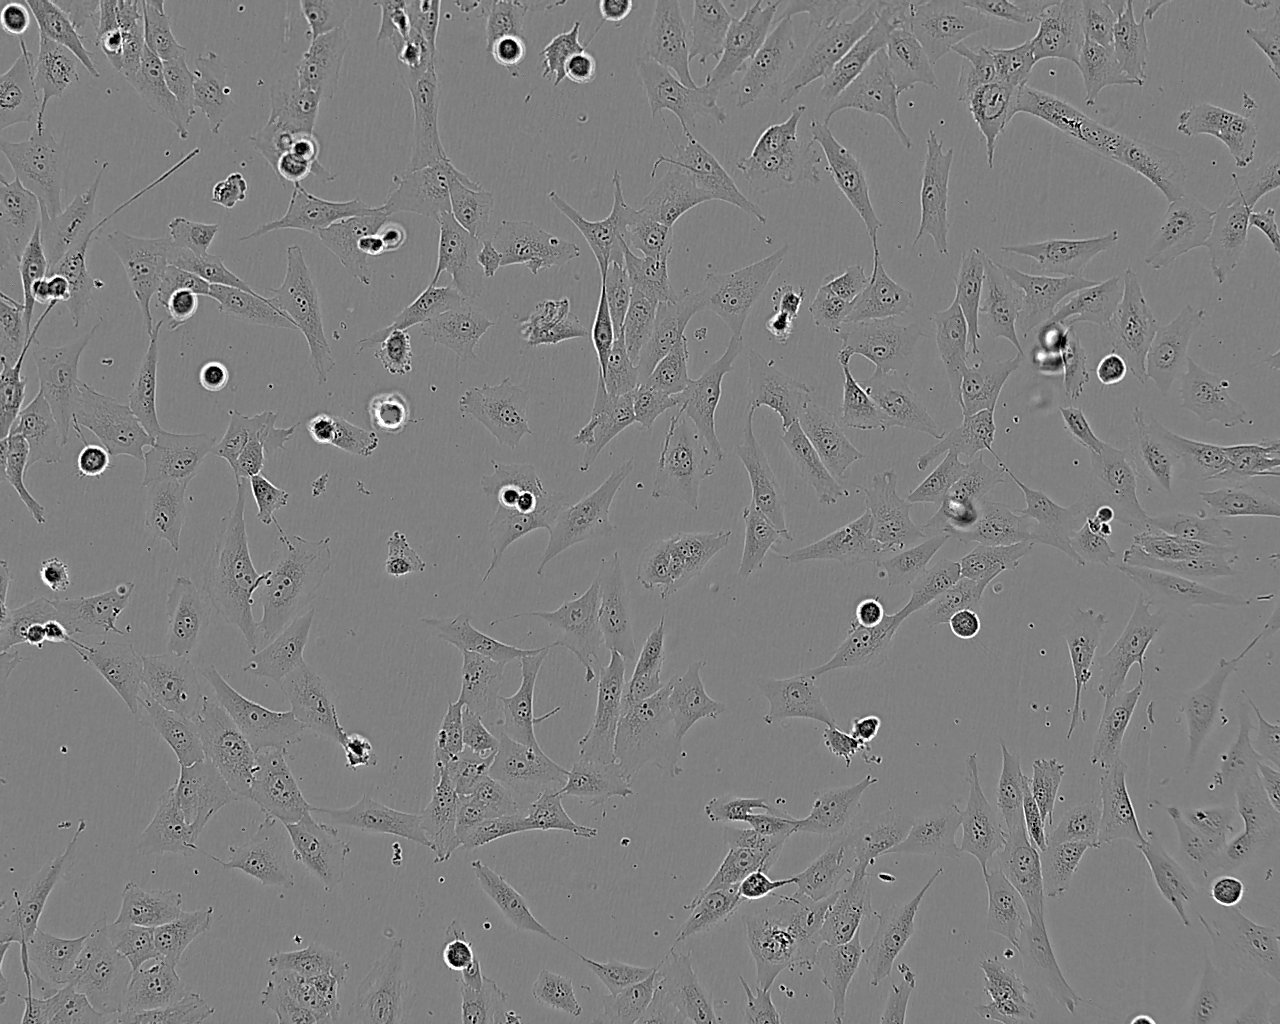

形态特征 上皮细胞样

生长特征 贴壁